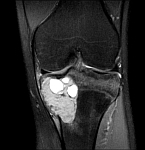

• Tumor surgery of the musculoskeletal system

• Resection of benign and malignant tumors of the bone and soft tissue

• Tumor total endoprosthesis (TEP) of all large joints and bones